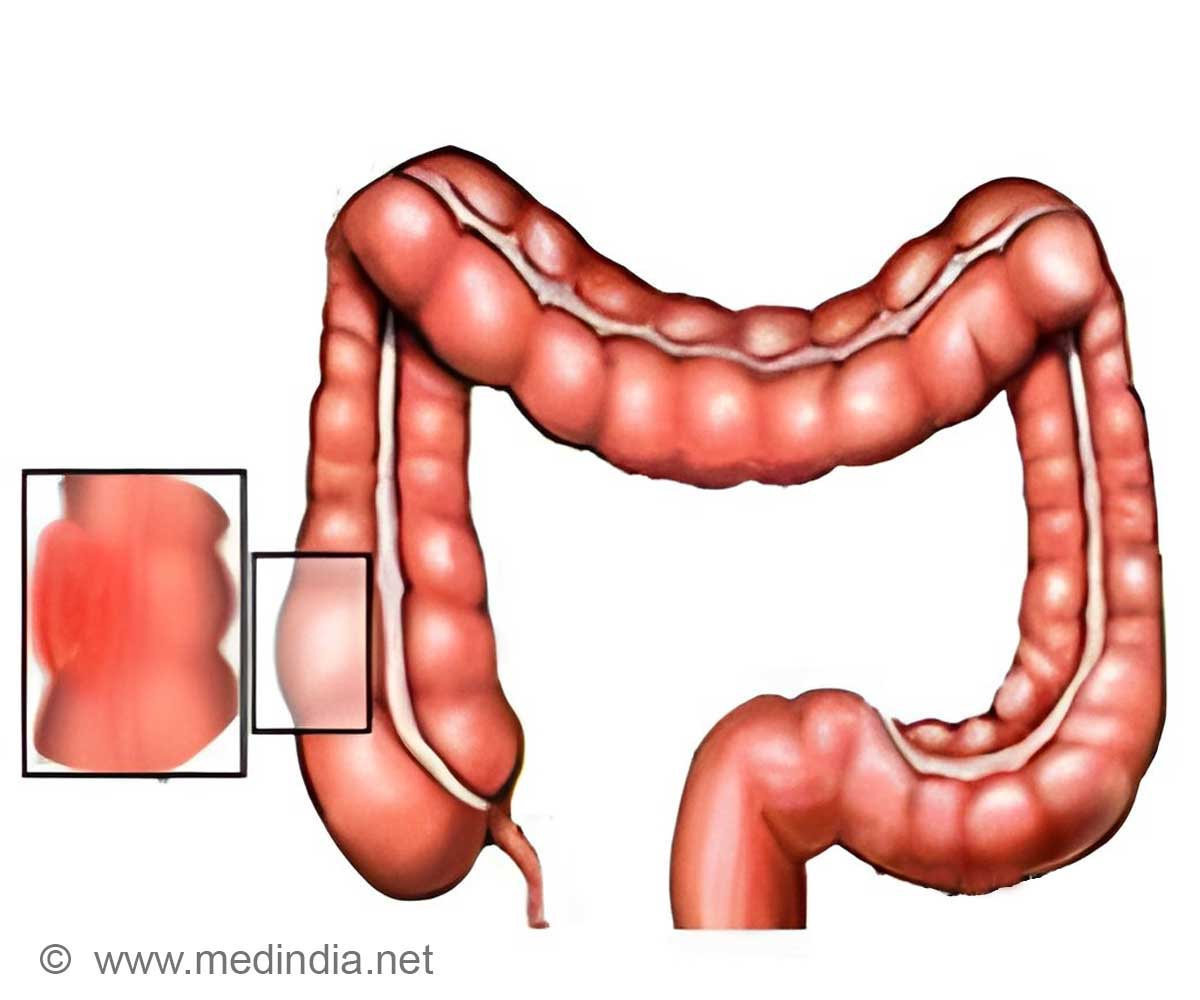

Mistletoe has been long associated with holiday romance but the plant may have another important use after researchers found that it can help treat colon cancer.

A team of researchers at University of Adelaide found that mistletoe extract can be more effective when dealing with colon cancer compared to chemotherapy without affecting the normal tissue cells that are also destroyed by conventional treatment.

“Our laboratory studies have shown Fraxini mistletoe extract by itself to be highly effective at reducing the viability of colon cancer cells. At certain concentrations, Fraxini also increased the potency of chemotherapy against the cancer cells”, lead researcher Zahra Lotfollahi.